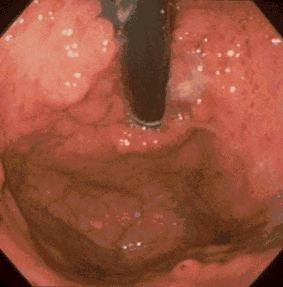

疾病(病理主体)的分类肿瘤样病变/幼年性息肉病

部位(按器官分)胃(部位)/其他

检查方法内窥镜